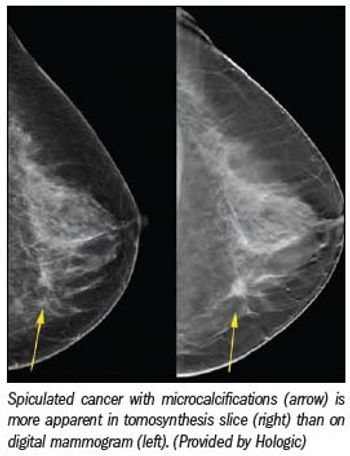

Breast tomosynthesis in the U.S. may finally be at hand. In September the FDA's Radiological Devices Panel unanimously agreed that Hologic's digital mammography tomosynthesis system, Selenia Dimensions, is effective and safe.